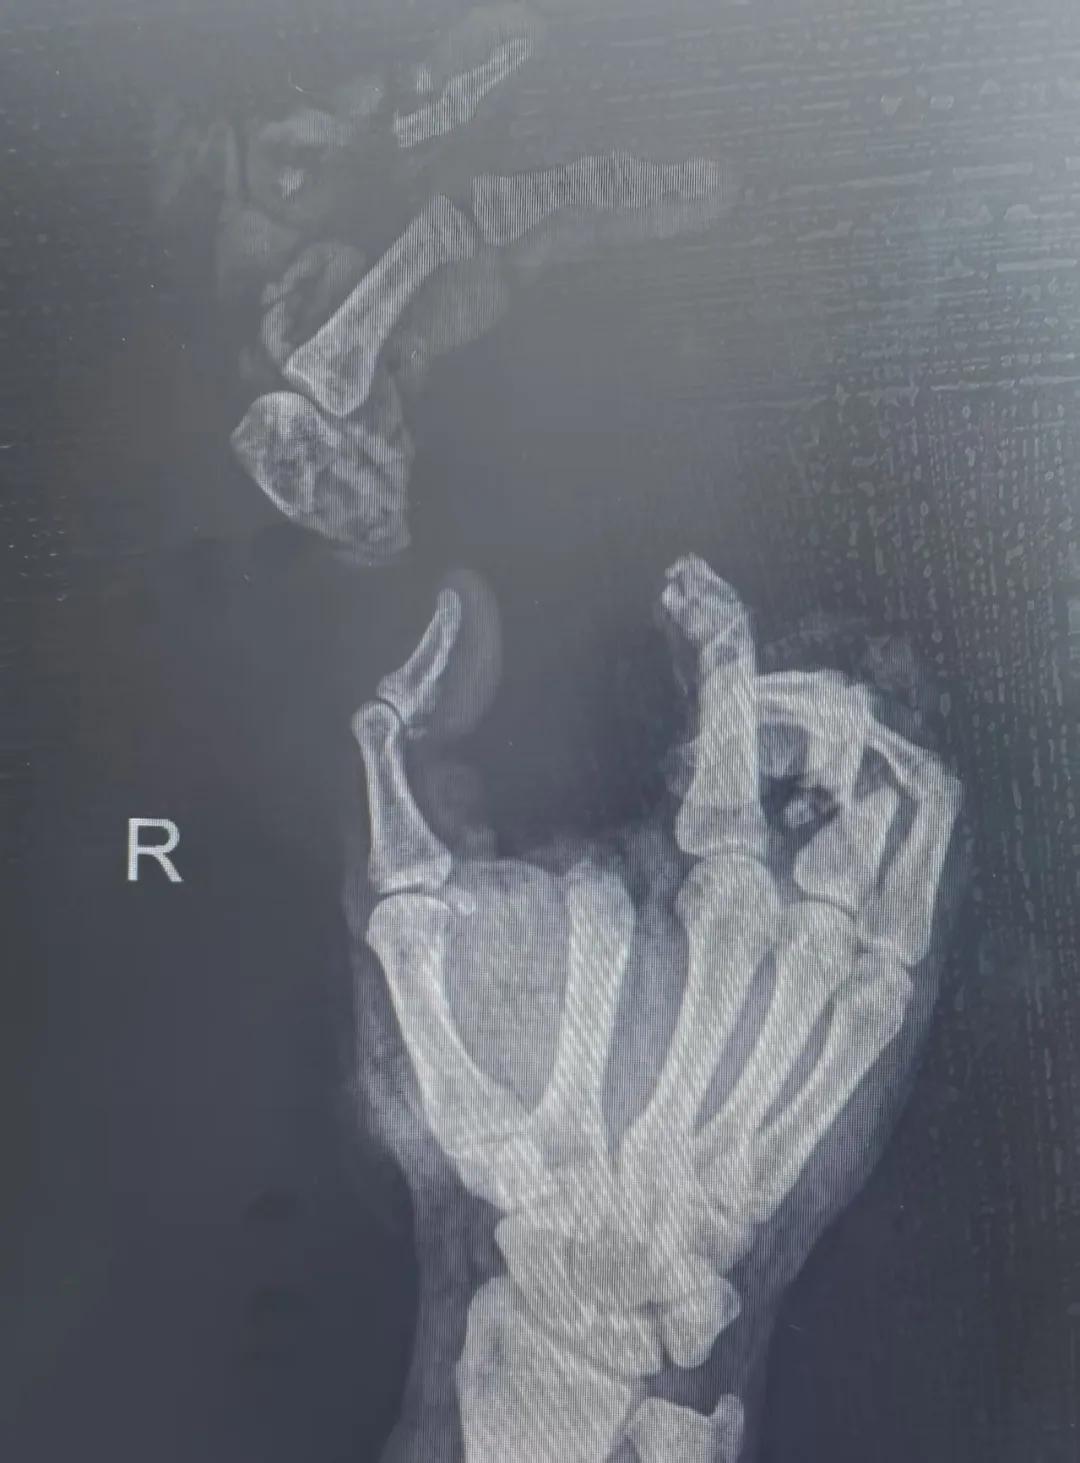

5月20日,市二院顯微外科燒傷整形科收治了3例因麥?zhǔn)毡晦r(nóng)機(jī)“咬傷”、農(nóng)具劃傷的患者。其中,56歲的劉某在收麥子時(shí)被打谷機(jī)皮帶絞傷右手,致手掌、食指、中指、環(huán)指嚴(yán)重毀損傷,骨、關(guān)節(jié)外露,因當(dāng)?shù)蒯t(yī)院無(wú)法治療,被家人緊急送往市二院顯微手足燒傷整形外科救治。“當(dāng)時(shí)整個(gè)右手血肉模糊,看上去都是爛的,我以為這個(gè)手是肯定保不住了。”患者家屬回憶當(dāng)時(shí)的場(chǎng)景仍然膽戰(zhàn)心驚。

患者入院后,經(jīng)X線檢查及創(chuàng)面檢查,醫(yī)生診斷為右手食指、中指及環(huán)指旋轉(zhuǎn)撕脫性離斷。接診的顯微手足燒傷整形外科醫(yī)護(hù)人員立即完善了各項(xiàng)術(shù)前準(zhǔn)備,并安排急診手術(shù)。因創(chuàng)面污染嚴(yán)重以及離斷肢體損傷程度較重,手術(shù)歷時(shí)近10小時(shí)。在沈衛(wèi)軍主任的帶領(lǐng)下,科室團(tuán)隊(duì)成功為其進(jìn)行了創(chuàng)面擴(kuò)創(chuàng)、斷肢再植術(shù),術(shù)后患指血運(yùn)良好,在進(jìn)一步觀察治療中。